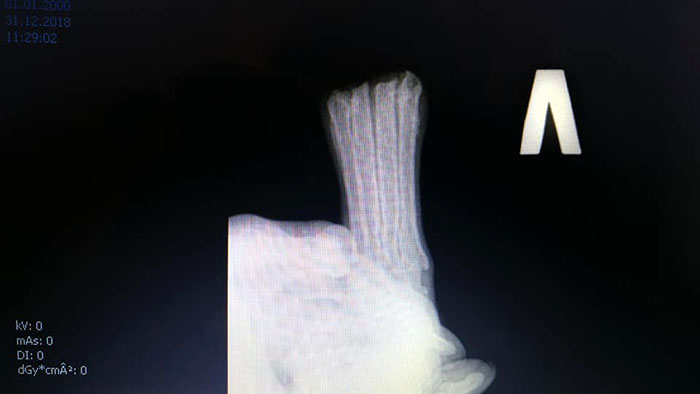

Как сообщила нашему изданию руководитель фонда "Друг" Наталья Титомир, медики, которые осматривали и оказывали первую помощь Санни - такую кличку дали собаке - после сделанного рентгена однозначно заявили, что характер травм у собаки позволяет сделать вывод о том, что увечья нанесены умышленно, каким-то острым предметом. То есть, собака пострадала не в результате несчастного случая.